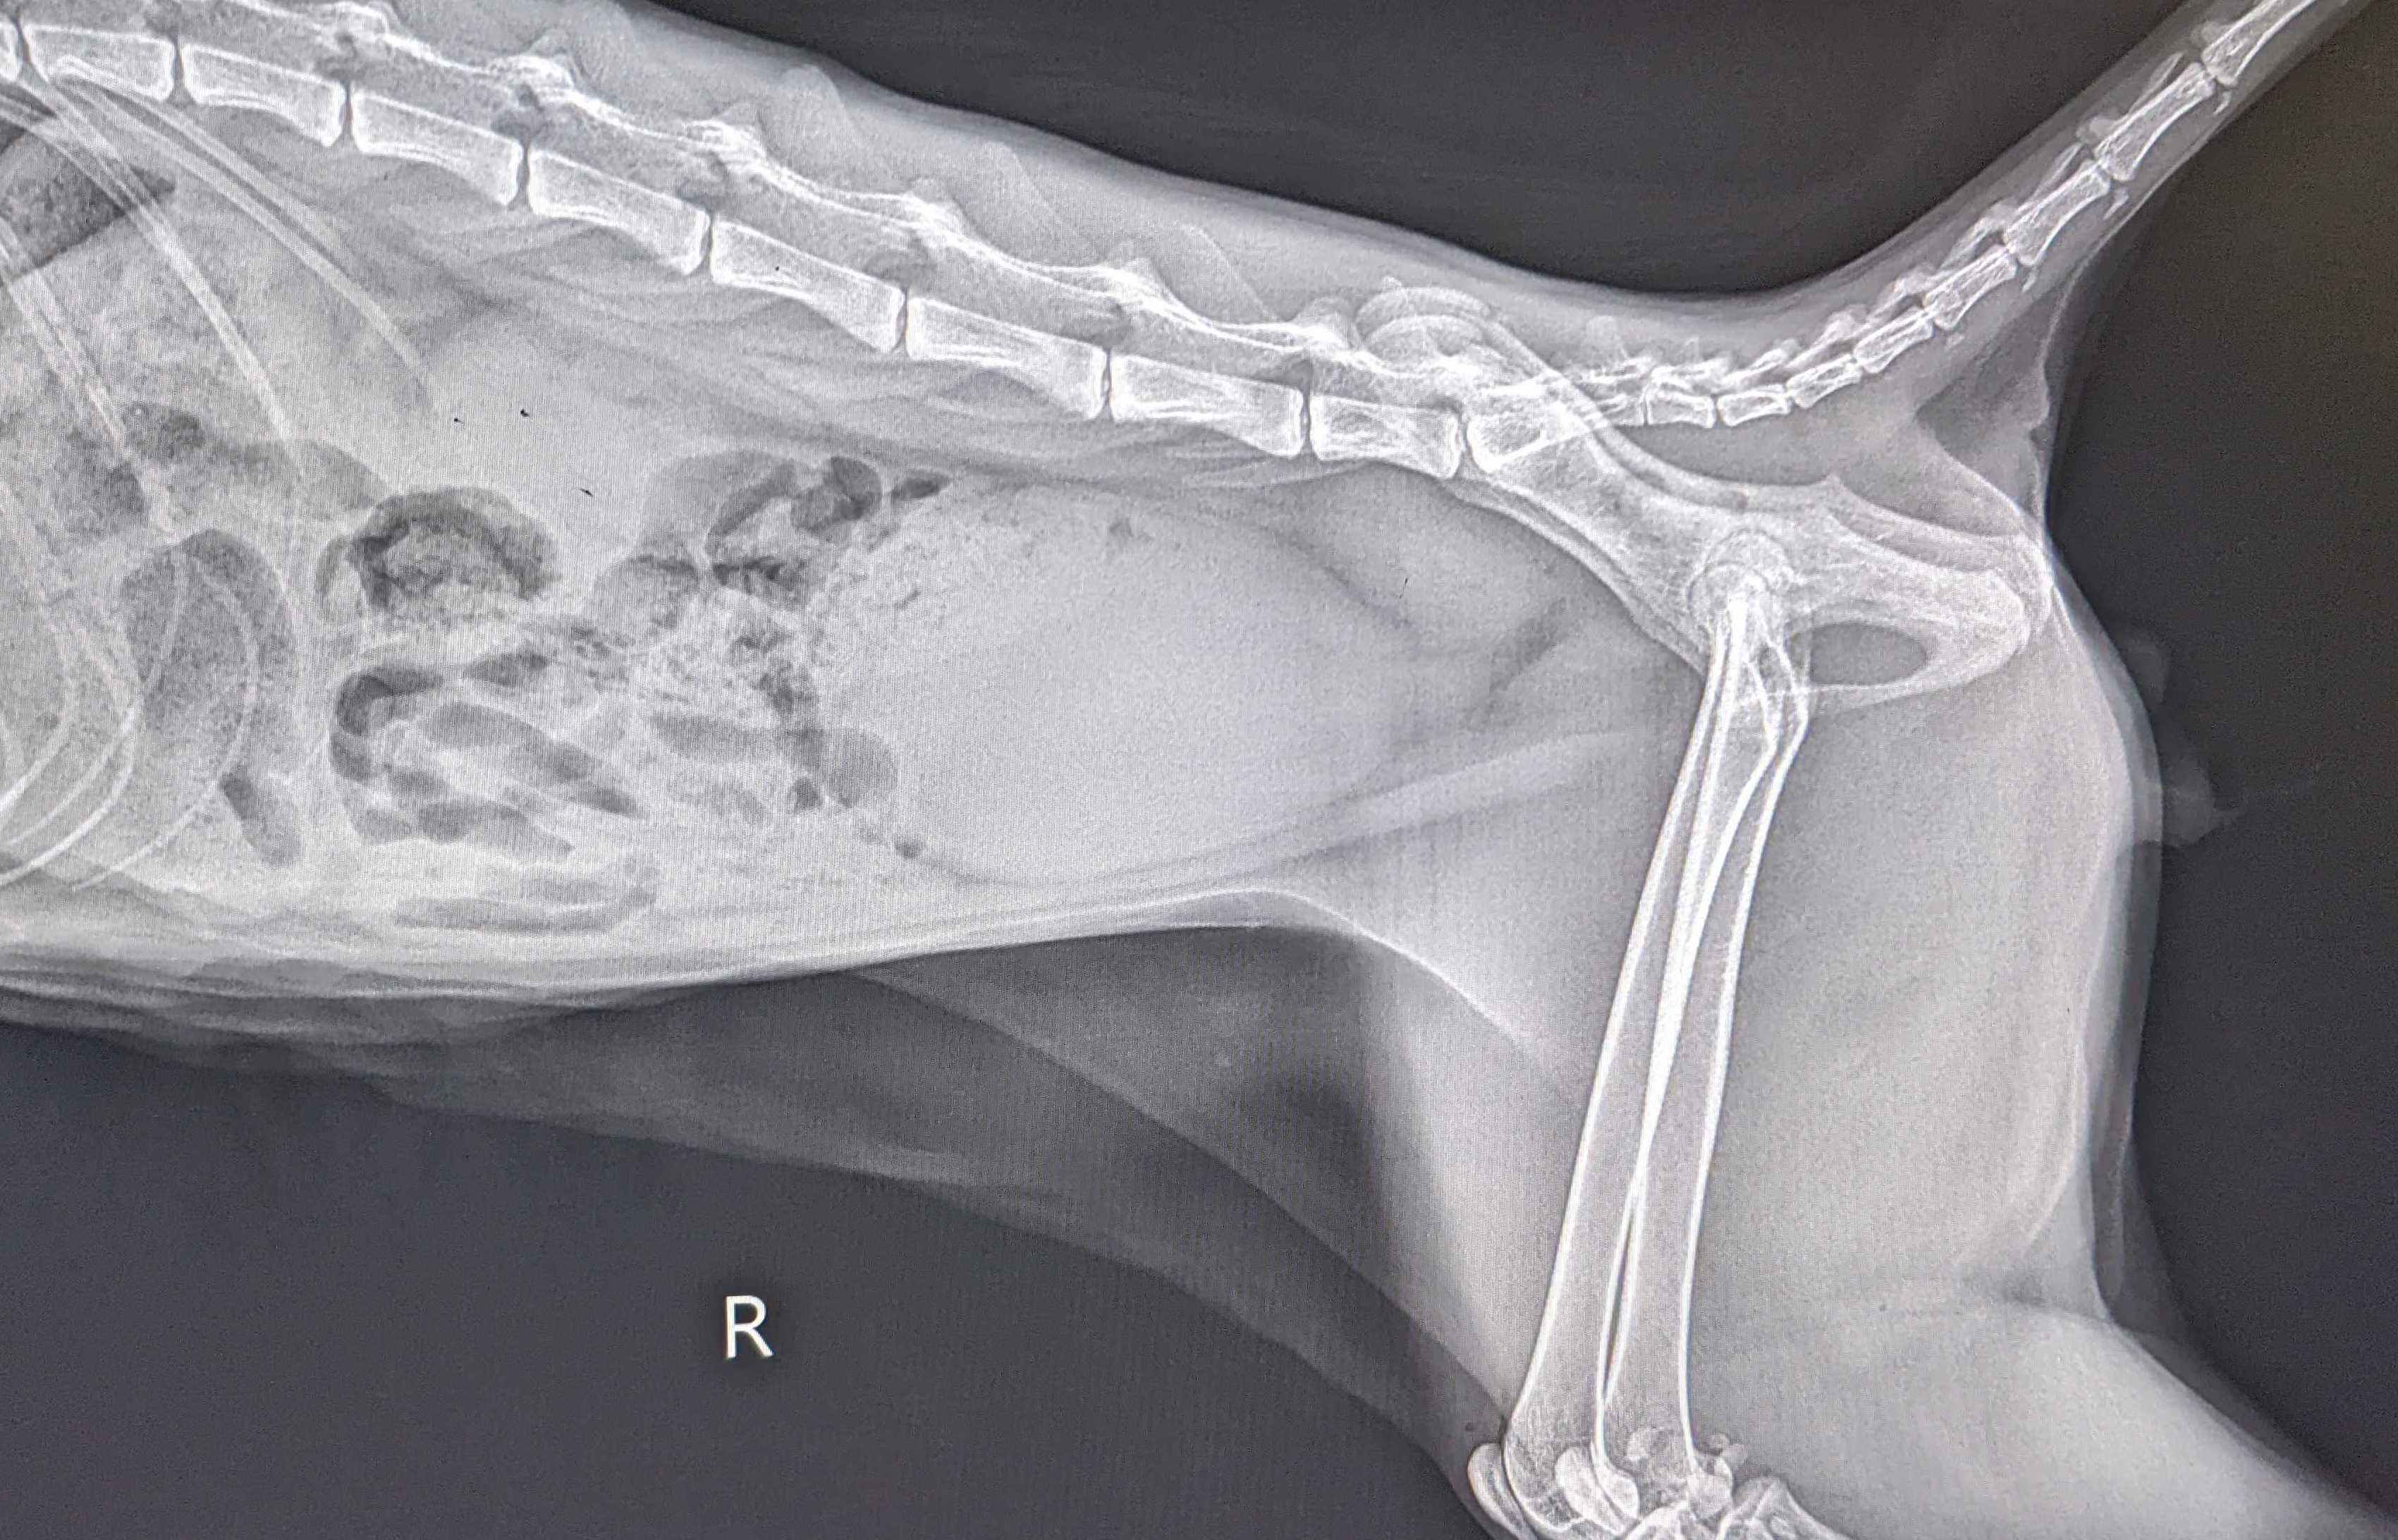

(写真中央)尿道閉塞で大量に尿が貯留した膀胱。ほかの臓器を押し出すようにお腹の大部分を占めている

長時間閉塞が続くと、膀胱がパンパンに張り、そのまま放置すると膀胱破裂を起こす場合もあります。破裂はしなくても、尿の流れがせき止められるため、その手前にある腎臓にも大きなダメージを与えてしまい、急性腎不全に進行することもあります。